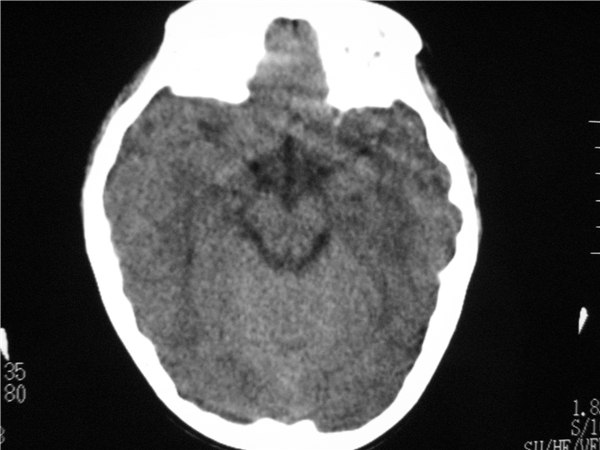

以下是引用随光逐影在2009-8-1 14:17:00的发言:[br]透明隔囊肿与vergae腔并存。

以下是引用zjzjr在2009-8-1 14:51:00的发言:[br]五、六脑室形成。